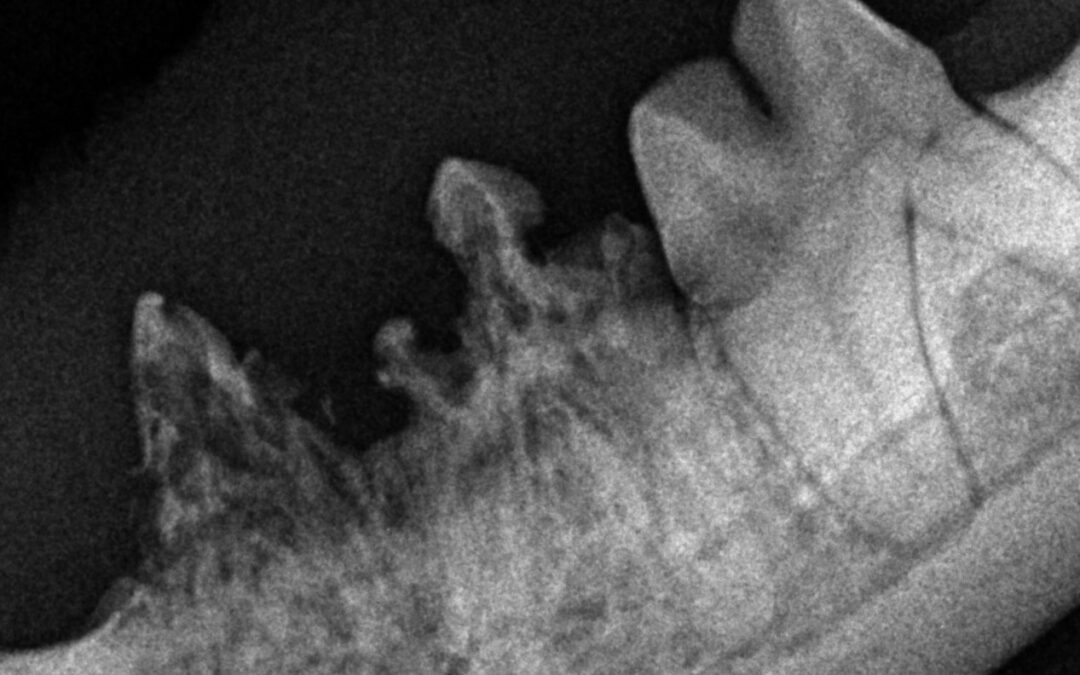

Was genau sind resorptive Läsionen (FORL)? Resorptive Läsion, bekannt auch als FORL (feline odontoklastische resorptive Läsionen), ist eine Erkrankung, bei der sich körpereigene Abwehrzellen gegen die Zähne richten. Die Zähne werden als Folge langsam vom Körper...